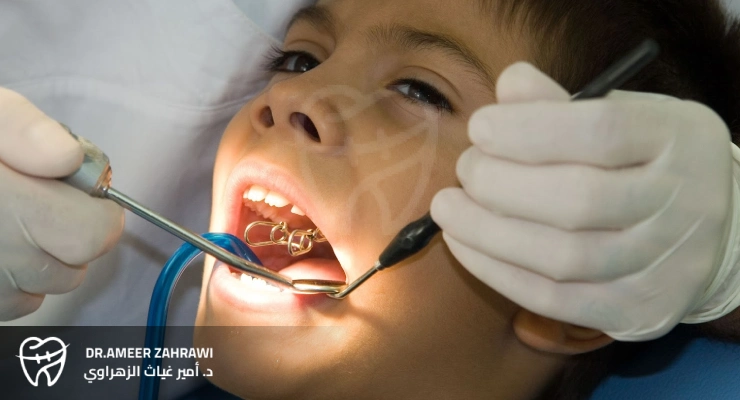

Dental fillings for children are a common pediatric dental procedure used to treat cavities in primary (baby) or permanent teeth. These fillings are usually made from materials such as composite resin or dental amalgam, and they are used to restore the tooth’s shape, function, and integrity after the decayed portion has been removed.Fillings help prevent further tooth decay, relieve pain, and restore the tooth’s strength so that your child can chew and speak properly. It’s essential for children to receive dental fillings in a timely manner to maintain good oral health and prevent more serious dental problems in the future.

Dental fillings are generally safe for children when performed by a qualified dentist using appropriate materials and techniques. The safety of fillings depends on several factors, including the type of filling material, the child’s overall health, the dentist’s skill, and proper oral care after the procedure.Factors that contribute to the safety of dental fillings in children include:

Before choosing the most suitable type of filling for a child, it’s important to consult a pediatric dentist. The dentist will recommend the best option based on the child’s specific needs and clinical situation.